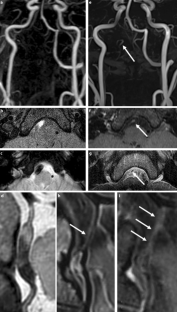

The HR-MRI findings were classified into complete normalization (normal lumen and wall with or without mild enhancement, n = 6), complete normalization with minimal wall changes (focal wall thickening with enhancement but normal luminal angiography, n = 8), incomplete normalization (focal wall thickening with enhancement with dilatation and stenosis on luminal angiography, n = 4), dissecting aneurysm (fusiform aneurysm with residual dissection findings, n = 8) and occlusion (small outer arterial diameter with diffuse contrast enhancement, n = 3).

The use of HR-MRI can demonstrate the distinguishing morphological features of chronic stage of spontaneous and unruptured ICAD as complete normalization, complete normalization with minimal wall changes, incomplete normalization, dissecting aneurysm and occlusion.